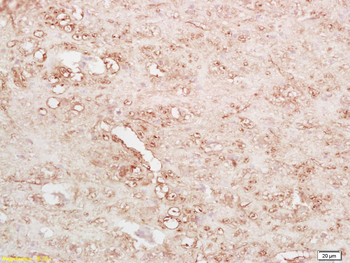

BNP Rabbit Polyclonal Antibody

IF, IHC-Fr, IHC-P

应用稀释比例:IHC-P=1:100-500, IHC-F=1:100-500, IF=1:100-500